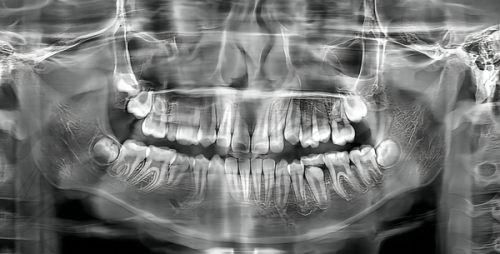

亮贝美口腔斥资引入口腔锥形束CT(CBCT)、iTero口内扫描仪等数字化设备。CBCT可提供严谨的三维颌骨和牙齿影像,避免传统二维片子的误差;iTero口扫能在数分钟内获取全口牙齿的数字模型,替代传统取模的不适感,并用于隐形矫正方案的设计和预览。

依托这些强大的数字化设备和软件,医院构建了完善的数字化正畸诊疗中 心。从诊断、方案模拟到隐形牙套的生产/监控、乃至精调阶段,数字化贯穿全程,提升了治疗的可预测性、精细度和效率。